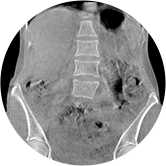

足踝

VR体绘制重建